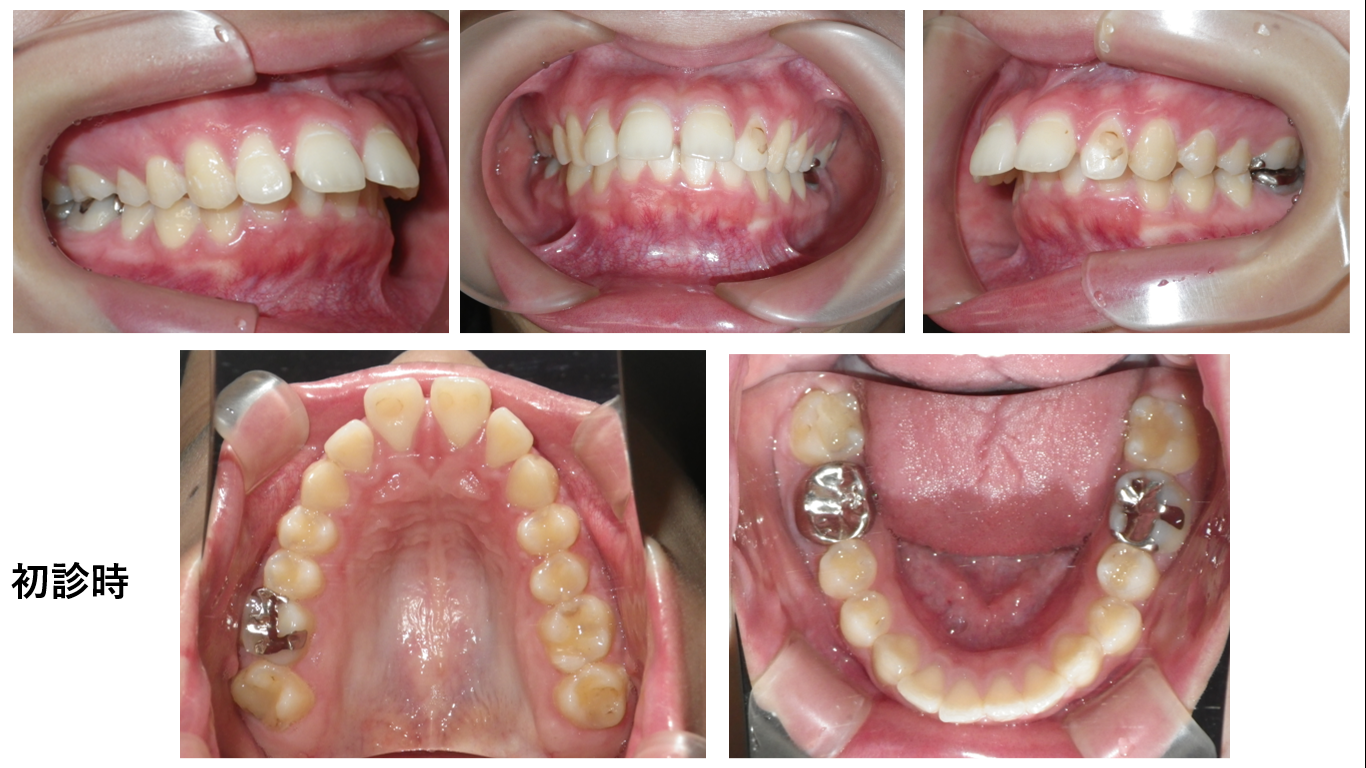

矯正症例143 AngleⅡ級2類、裏側矯正、舌側矯正

治療開始年齢24歳、治療期間3年、抜歯部位:下顎左右5番、上顎左右4番、治療費総額1,310,000(税込み)歯列矯正には以下のリスクを伴う場合があります。1最初は矯正装置による不快感、痛み等がありま...